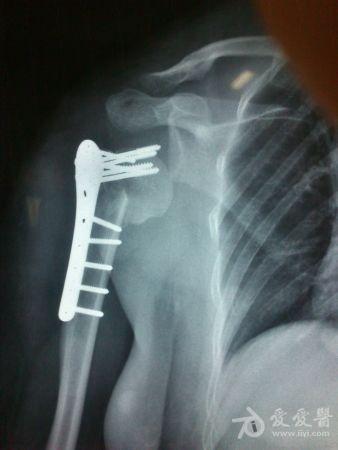

病史特点及病情摘要:1、患者女性,51岁。2、患者自诉入院前1年余因右肱骨外科颈骨折在外院行切开复位内固定术,术后右肩关节疼痛、活动受限,一直未予处理,今为明确诊治入院。患者精神、食欲、睡眠尚可。3、既往史、个人史、家族史无特殊。4、入院查体:生命征平稳,心肺腹检查未见异常,NS(-)。专科情况:右上臂近端内侧见一约15cm手术切口疤痕,愈合佳,右肩关节能外展20度,前屈、后伸及旋前、旋后功能障碍,余关节活动好。舌质红,苔薄白,脉实。5、辅助检查:右肩关节正侧位片:右肱骨外科颈骨折内固定术后再骨折伴右肩关节脱位。

诊疗计划:????前两张片是院外术前,中间两张是院外术后,后两张是在我院照。 术前

院外术后

同意楼主观点,患者第一次手术复位欠佳,但可勉强接受。但钉子穿出,是手术后肩关节疼痛的主要原因,现在看骨折已愈合,头无明显头坏死迹象,只需取出内固定,麻醉下活动肩关节,使肩关节活动度改善,术后加强功能锻炼,应该恢复不错。